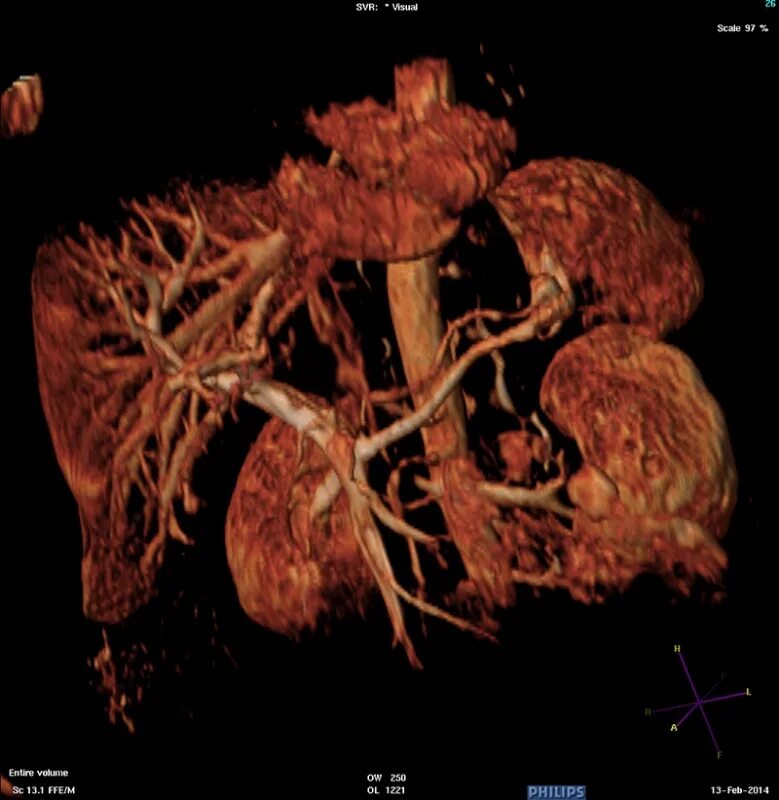

Забрюшинная онкология